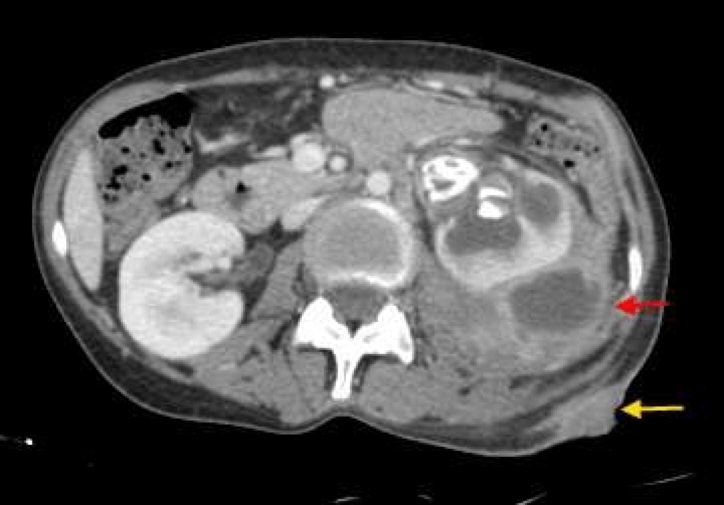

Renal and perinephric abscesses are serious complications of urinary tract infections, most commonly developing following unresolved or severe pyelonephritis. Caused most frequently by Escherichia coli, these abscesses can occur within the renal parenchyma or the perinephric space surrounding the kidney. Clinical presentation may mimic pyelonephritis but tends to be more severe and persistent, and often requires imaging for diagnosis. Prompt drainage and targeted antibiotic therapy are essential to prevent progression to sepsis or long-term renal damage.

A renal abscess is a collection of pus within the kidney tissue, whereas a perinephric abscess involves the space around the kidney. Both are complications of upper urinary tract infections and require urgent medical attention.

- Imaging is essential:

- CT abdomen – gold standard for diagnosis and localisation

- Ultrasound (USS) – may detect larger fluid collections